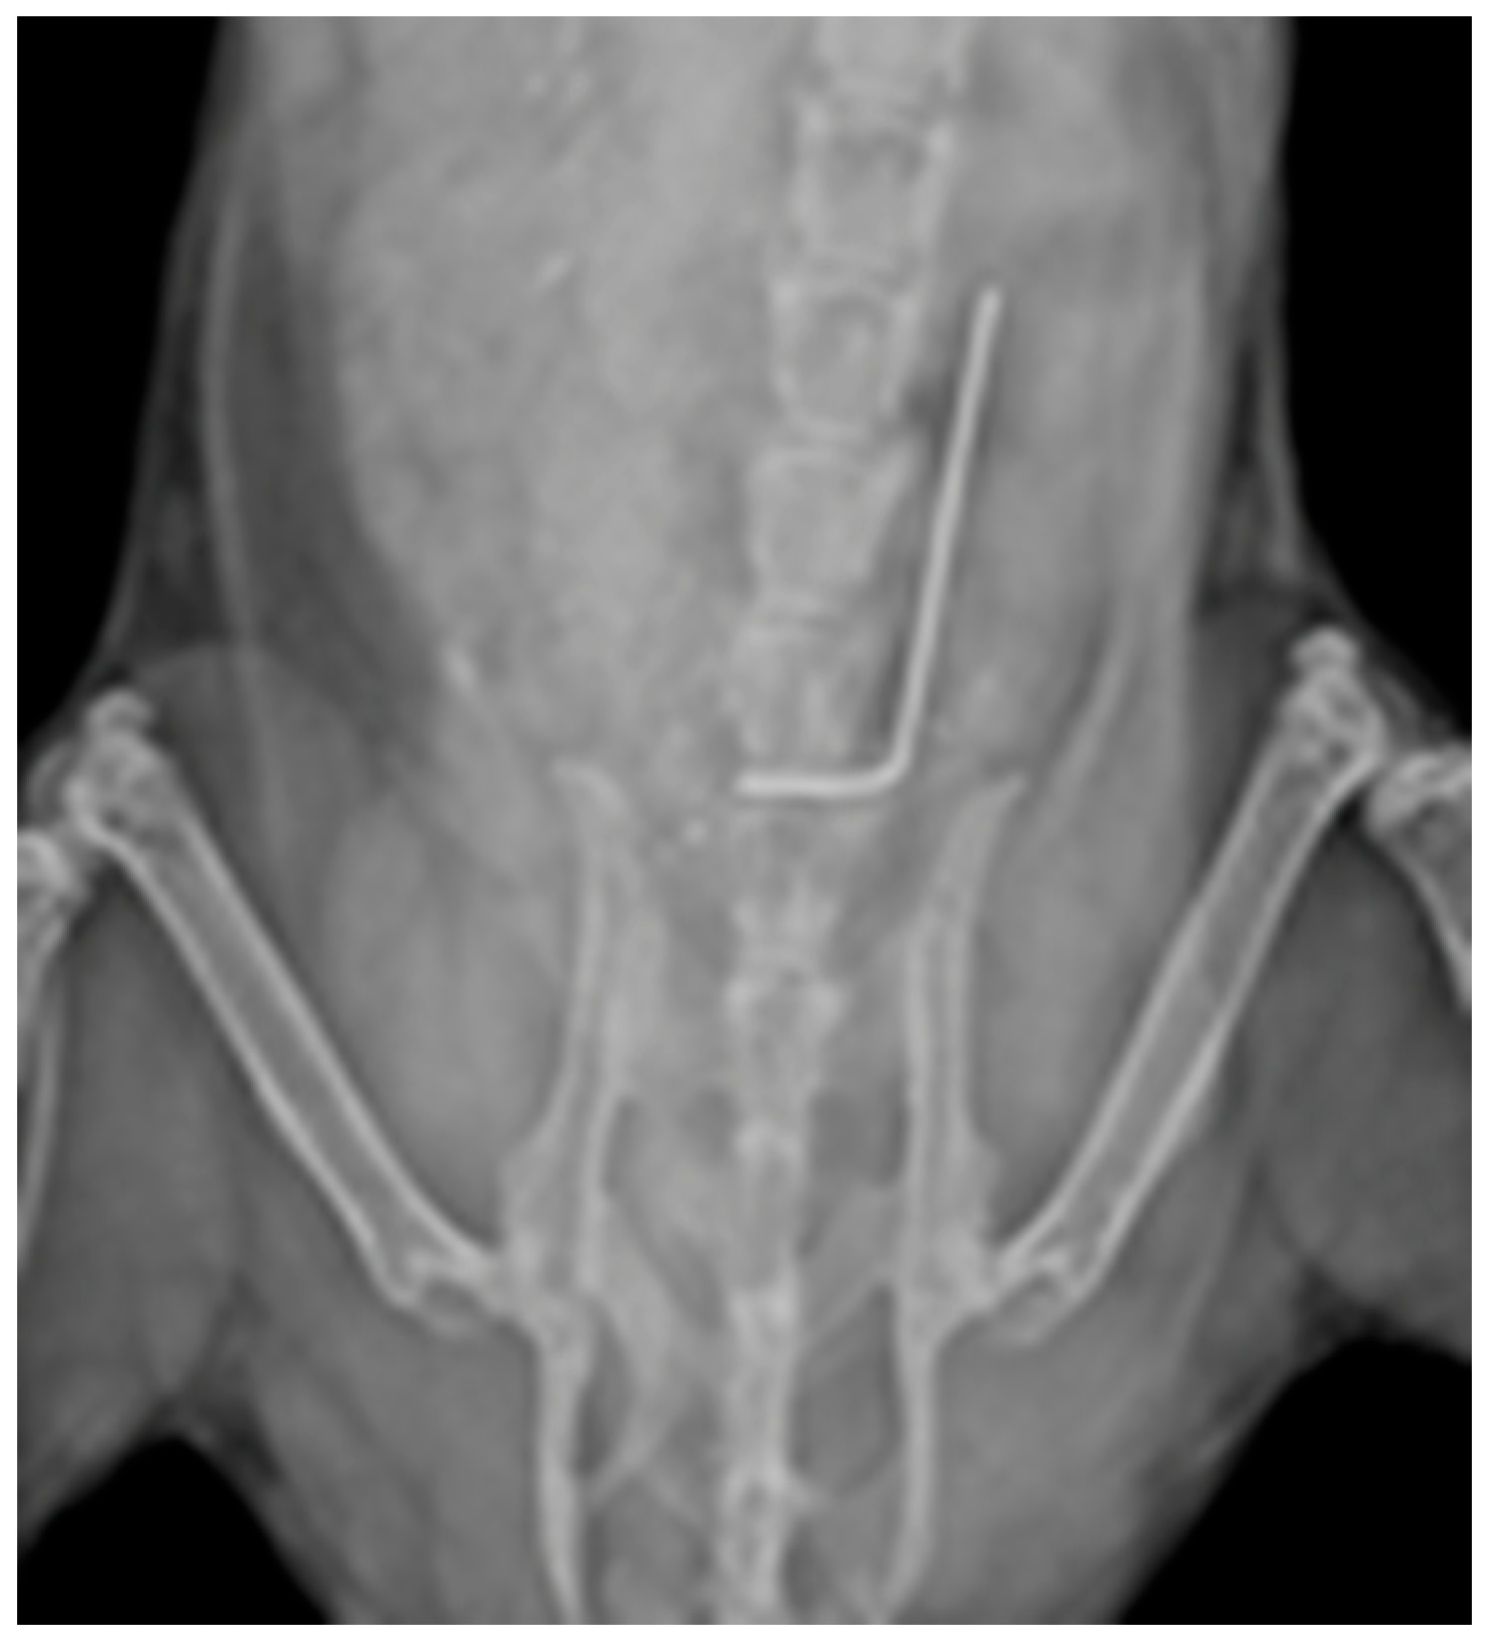

4.7. Antibody and Antibiotic Administration